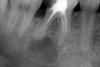

Dr.Sapronov Опубликовано 21 октября, 2012 Поделиться Опубликовано 21 октября, 2012 Пациентка 28 лет, направлена терапевтом для уточнения плана лечения 36 зуба( перелечивать каналы он не будет). Жалобы на боли при накусывании, вертикальная перкуссия болезненна, по переходной складке все спокойно, на снимке киста 36 зуба. Ваше мнение делать резекцию или удалять? От многих коллег слышал что резекция верхушек боковой группы зубов неблагодарное занятие и прогноз не благоприятный( через некоторое время рецидивы). 90% что удалять. По снимку видно разряжение кости в области бифуркации, гранулема очень больших размеров и вероятность в том, что каналы будут перелечены нет, так как там еще что то похожее на инструмент. Еще раз повторюсь - я бы удалил 1 Ссылка на комментарий

Orient Опубликовано 21 октября, 2012 Поделиться Опубликовано 21 октября, 2012 в обл бифуркации разряжения нету,если пац согласиться на каналыи удасться их пройти, то зуб жилец! Ссылка на комментарий

ger_berra Опубликовано 22 октября, 2012 Поделиться Опубликовано 22 октября, 2012 в обл бифуркации разряжения нету,если пац согласиться на каналыи удасться их пройти, то зуб жилец!"Разряжение" в фуркации ещё не повод для удаления. Ссылка на комментарий

ger_berra Опубликовано 24 октября, 2012 Поделиться Опубликовано 24 октября, 2012 как часто получается справиться с разряжением бифуркации???Сначала нужно определить причину,а потом махать саблей.Если это пропущенная анатомия,неадекватная обработка,наличие(или предположение) латерали,то правильная эндодонтия и есть лечение.Если гнилая перфорация,то естественно,удаление. 3 Ссылка на комментарий